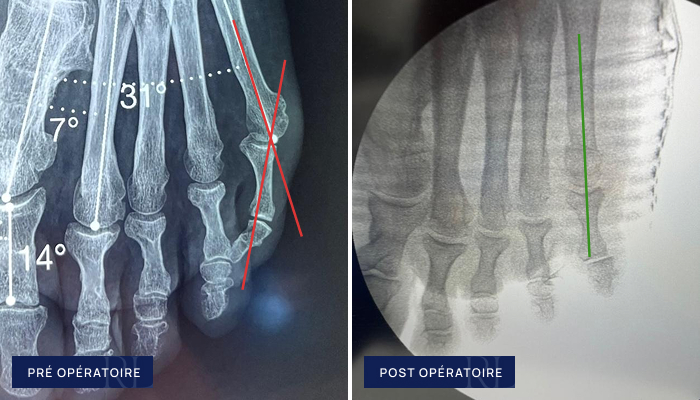

Radiographies pré et post opératoire d’un Quintus varus

À gauche : Déformation du petit orteil (quintus varus du pied)

À droite : Correction mini invasive (ostéotomies percutanées)